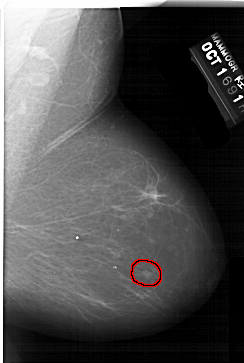

A_1542_1.RIGHT_CC

RIGHT_CC LINES 6871 PIXELS_PER_LINE 4576 BITS_PER_PIXEL 12 RESOLUTION 43.5 OVERLAY

FILE: A_1542_1.RIGHT_CC.OVERLAY

TOTAL_ABNORMALITIES 1

ABNORMALITY 1

LESION_TYPE MASS SHAPE LOBULATED MARGINS CIRCUMSCRIBED

ASSESSMENT 4

SUBTLETY 3

PATHOLOGY BENIGN

TOTAL_OUTLINES 1

BOUNDARY